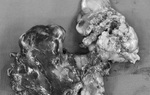

Kết quả sinh thiết giải phẫu bệnh cho thấy hai bệnh nhân trên đều bị Lymphangioma Cirumscriptum (LC) là bệnh u bạch huyết hay còn được gọi là khối u ở âm hộ, là một bệnh hiếm gặp.